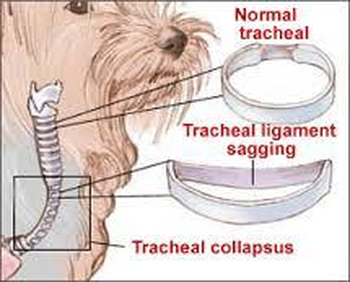

Tracheal Collapse In Dogs Signs Causes Treatment And More Dutch

Tracheal Collapse in Dogs Complete Guide Clinician s Brief

The Veterinary Nurse Anaesthetic management of a patient undergoing dental extractions with concurrent congestive heart failure and advanced tracheal collapse

Tracheal Collapse In Dogs What It Is Symptoms To Look For And How To Treat It Trudell Animal Health

Tracheal Collapse Meadows Veterinary Clinic of East Peoria